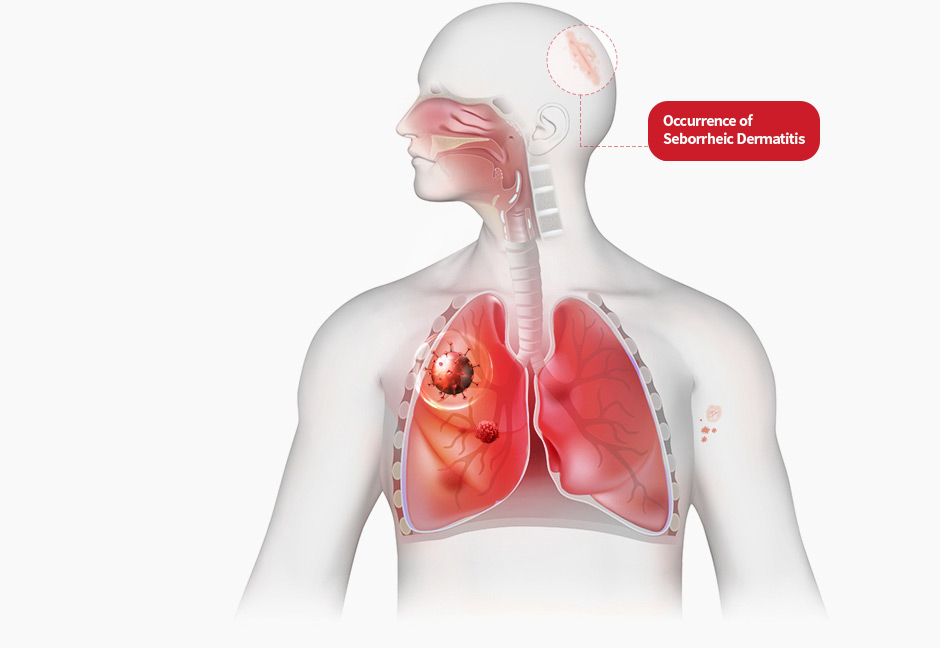

Maintain Cleanliness

For seborrheic dermatitis, keeping your hair and skin clean is crucial.

Removing scalp oil and dust helps eliminate aggravating factors.

If the condition is severe, shampooing 5 times a week is recommended;

otherwise, 3 times a week is sufficient. Use shampoo rather than soap.

Avoid Hair Styling Products

Products like mousse, spray, and gel can combine with scalp oil

and irritate the scalp. It's best to avoid using them,

and if used, wash them off as soon as possible with a shower.